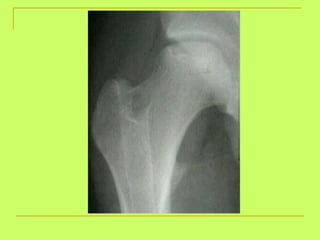

What is the age ? >18 years (united head of femur)

What is the age? above18ys

Age from lower limb examination 1) Lesser trochanter  (16y )-----Greater trochanter  (17y)  ------ Head of the femur  (18y). 2) Lower end of the femur + shaft  (21y). 3) Upper end of the tibia +shaft  (21y). 4) Lower end of the tibia +shaft  (18 y).   By foot examination ossific center appears at calcanium at  6 years  and union of epiphysis at the calcanium at  14 years  ,so examining only this bone gives us a range of 8 years